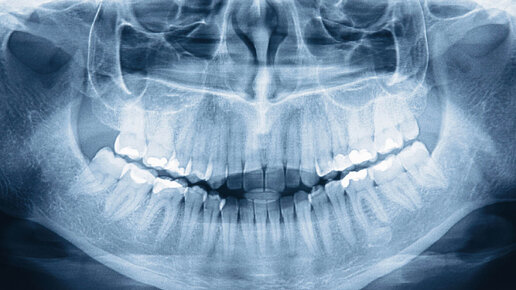

Рентген зубов и челюстей

Часто сделать снимок зуба бывает необходимо для своевременной диагностики потенциальных проблем. Это привычная многим процедура, как показывают консультации врача онлайн, все равно таит в себе множество вопросов. Ответы врачей на самые распространенные заблуждения о рентгене зубов читайте в нашем материале. Подписывайтесь на нас в социальных сетях Вконтакте Instagram Facebook На бесплатных консультациях врачей часто спрашивают, не вредно ли рентгеновское излучение, когда делаешь снимок зуба. По...